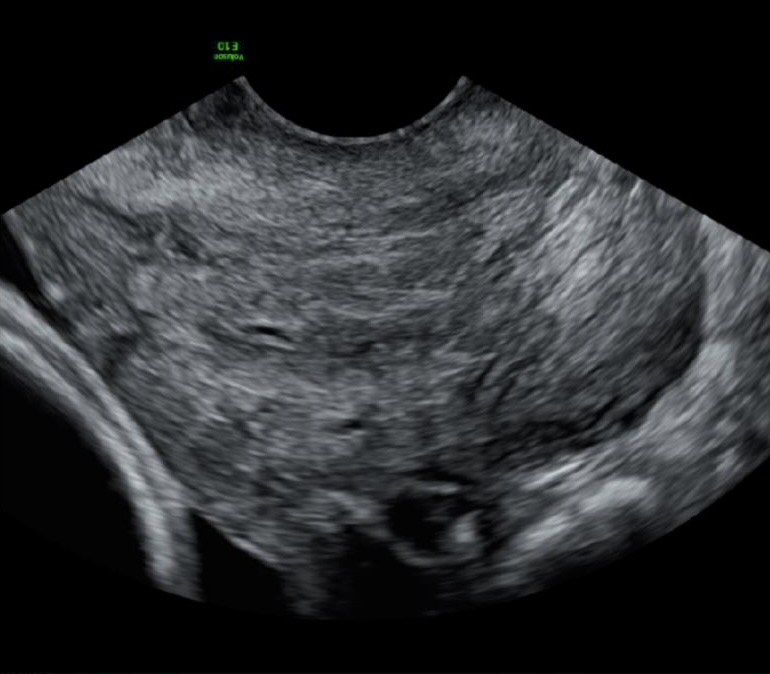

4. Accurately determining cervical funnelling

The key to deciding whether there is actually cervical funnelling is to assess whether the membranes bulge into the cervical canal. With true cervical funnelling the membranes will always bulge into the cervical canal.

Figure 2a. Example of long and closed cervix, without funnelling, showing the membranes covering the internal os.